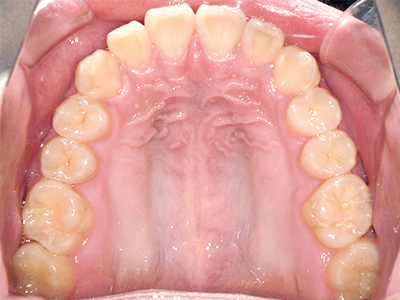

↓ - 頬の圧力が上の歯列にかかりやすくなる

↓ - 上あごが狭くなる

ないき歯科クリニックでは、上あごの成長不足を補い、鼻呼吸を獲得しつつ歯列を整え、将来のお口をより健康な状態にすることをゴールに定める矯正治療をおこなっています。